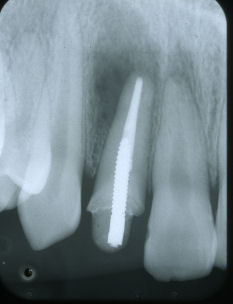

右上1番の歯根の先に膿がたまっています。冠をはずして根の治療をしました。

数年後膿は消えています。

根の先をいかに緊密に圧力かけて密閉するかが問題なのです。

歯内療法